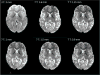

Whole-brain functional magnetic resonance imaging (fMRI), in conjunction with multiband acceleration, has played an important role in mapping the functional connectivity throughout the entire brain with both high temporal and spatial resolution. Ultrahigh magnetic field strengths (7T and above) allow functional imaging with even higher functional contrast-to-noise ratios for improved spatial resolution and specificity compared to traditional field strengths (1.5T and 3T). High-resolution 7T fMRI, however, has primarily been constrained to smaller brain regions given the amount of time it takes to acquire the number of slices necessary for high resolution whole brain imaging. Here we evaluate a range of whole-brain high-resolution resting state fMRI protocols (0.9, 1.25, 1.5, 1.6 and 2mm isotropic voxels) at 7T, obtained with both in-plane and slice acceleration parallel imaging techniques to maintain the temporal resolution and brain coverage typically acquired at 3T. Using the processing pipeline developed by the Human Connectome Project, we demonstrate that high resolution images acquired at 7T provide increased functional contrast to noise ratios with significantly less partial volume effects and more distinct spatial features, potentially allowing for robust individual subject parcellations and descriptions of fine-scaled patterns, such as visuotopic organization.